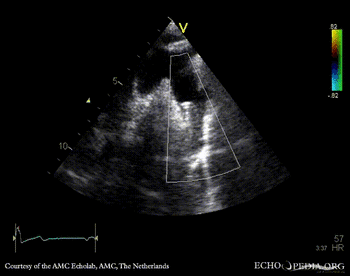

Suprasternal view: stent in aorta descendends, status after correction of coarctatio aortae Suprasternal view with color doppler